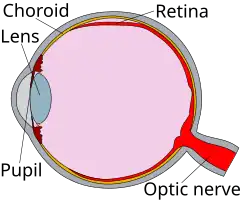

The retina is a thin layer at the back of the eye that processes visual information and sends it to the brain.[5] When the retina detaches, common symptoms include seeing floaters, flashing lights, a dark shadow in vision, and sudden blurry vision.[1][3] The most common type of retinal detachment is rhegmatogenous, which occurs when a tear or hole in the retina lets fluid from the center of the eye get behind it, causing the retina to pull away.[6]

The retina is a thin layer of tissue located at the back of the eye.[1][5] It processes visual information and transmits it to the brain.[5] Retinal detachment occurs when the retina separates from the layers underneath it.[2] This impairs its function, potentially leading to vision loss.[2][4] Retinal detachment often requires urgent medical intervention to prevent permanent vision loss.[3]